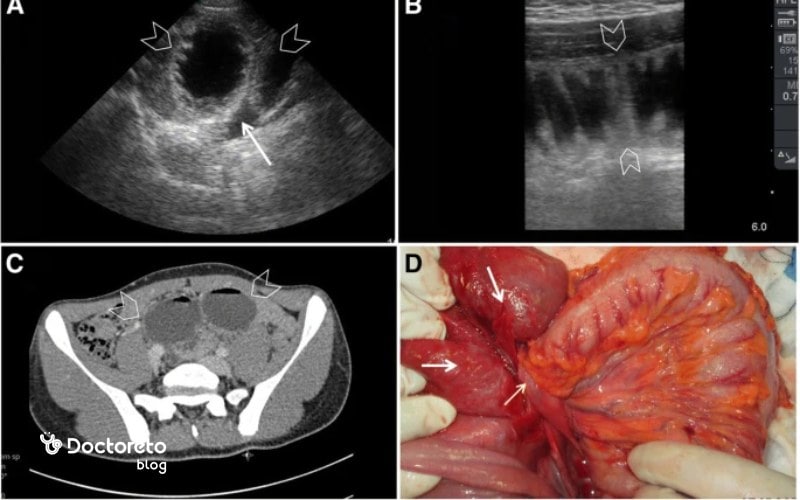

اما نتایج غیرنرمال ممکن است نشانهای از مشکلات جدیتر در روده باشد. یکی از مهمترین یافتههای غیرنرمال در سونوگرافی، تودهها یا ضخامت غیرطبیعی دیواره روده است. ضخیم شدن دیواره روده میتواند نشاندهنده التهاب، عفونت یا حتی سرطان باشد.

تومورهای سرطانی معمولاً باعث تغییرات ساختاری در دیواره روده میشوند که به وضوح در تصاویر سونوگرافی قابل مشاهده هستند. در این حالت، پزشک ممکن است از بیمار بخواهد که آزمایشهای بیشتری مانند کولونوسکوپی یا بیوپسی برای تایید تشخیص انجام دهد.

علاوه بر این، سونوگرافی قادر است غدد لنفاوی بزرگشده را نیز شناسایی کند. غدد لنفاوی بزرگ شده میتوانند نشانهای از انتشار سرطان به این اندامها باشند، زیرا سیستم لنفاوی بهطور معمول اولین مقصد برای متاستازهای سرطان است. شناسایی این غدد لنفاوی میتواند پزشکان را آگاه کند تا در کاهش گسترش سرطان به دیگر نواحی بدن درمان مناسبی را تجویز کنند.

یکی دیگر از نتایج غیرنرمال در سونوگرافی، ضایعات کبدی است که میتواند به متاستازهای کبدی اشاره داشته باشد. سرطان روده بهویژه در مراحل پیشرفته، بهطور شایع به کبد متاستاز میکند و سونوگرافی میتواند تصاویر دقیقی از وضعیت کبد ارائه دهد. در صورتی که ضایعات کبدی در سونوگرافی مشاهده شود، این نیاز به آزمایشهای بیشتر مانند سیتیاسکن یا امآرآی برای ارزیابی دقیقتر گسترش سرطان به کبد دارد.